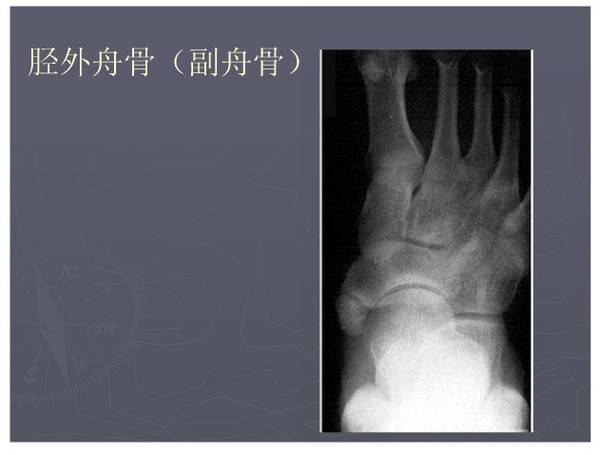

常见异常副骨或籽骨

在足部发生率最高,如副舟骨、距上骨、胫下骨腓小骨等